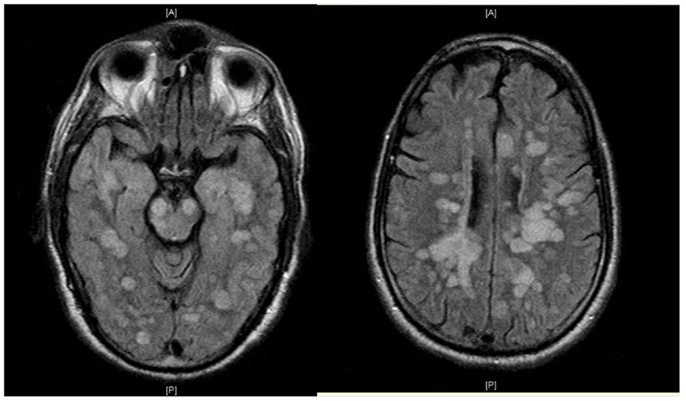

Информация о диссеминированном рассеянном энцефаломиелите